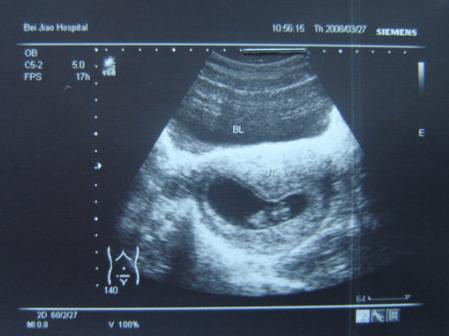

果不其然,她这么着急确实是和肚里宝宝有关。当初自己用验孕棒查出怀孕时,小唐怕结果不准确,我就陪着她去了一次医院,B超结果显示孕囊已经形成,宝宝已经44天了。

准妈妈们在察觉到经期异常或是孕吐、嗜睡等早孕反应后,通常都会来到医院进一步确定,此时安排B超是非常稳妥的方式。B超不仅能确定女性是否怀孕,观察胚胎发育情况,还能作为推算怀孕时间的佐证。

有过怀孕经历的宝妈都知道,在第一次就诊时如果刚刚怀孕,在B超影像中我们通常只能看到一个小孕囊,但是医生从孕囊上获取的信息则非常多。

首先医生会观察孕囊是否已经形成,以及孕囊的大小,发育到何种程度,再结合宝妈月经周期推断较为准确的怀孕天数。观察内容还包括孕囊的位置,以此排除宫外孕和瘢痕妊娠的可能。